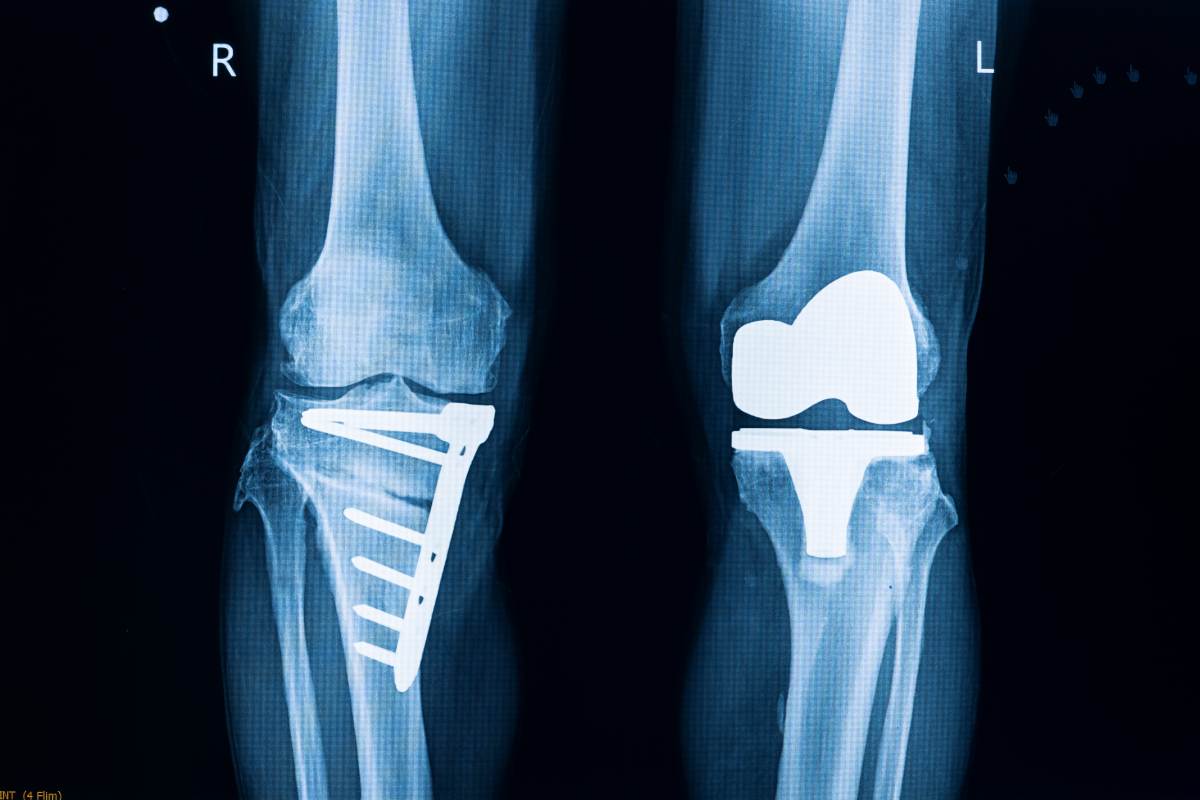

Knee Recall Lawsuit . Exactech recalled all optetrak, logic and truliant knee replacement devices on february 7, 2022. A recalled knee replacement system has kicked off new product liability litigation in georgia after a recipient alleged portions of the. And has been associated with early. The exactech recall includes an estimated 147,000 knee replacement implants in the u.s. People filed exactech lawsuits after the company recalled thousands of hip, knee, ankle and shoulder devices in 2021, 2022 and 2024 due to defective packaging. According to lawsuits, the defective devices caused devices to fail early, leading to additional surgery. Burke’s exactech recall lawsuit asserts that the premature failure of his exactech knee implants after just six years was a direct. In a torrent of lawsuits, patients accuse florida device maker exactech of hiding knee and hip implant defects for years.

A recalled knee replacement system has kicked off new product liability litigation in georgia after a recipient alleged portions of the. And has been associated with early. Exactech recalled all optetrak, logic and truliant knee replacement devices on february 7, 2022. In a torrent of lawsuits, patients accuse florida device maker exactech of hiding knee and hip implant defects for years. The exactech recall includes an estimated 147,000 knee replacement implants in the u.s. Burke’s exactech recall lawsuit asserts that the premature failure of his exactech knee implants after just six years was a direct. According to lawsuits, the defective devices caused devices to fail early, leading to additional surgery. People filed exactech lawsuits after the company recalled thousands of hip, knee, ankle and shoulder devices in 2021, 2022 and 2024 due to defective packaging.